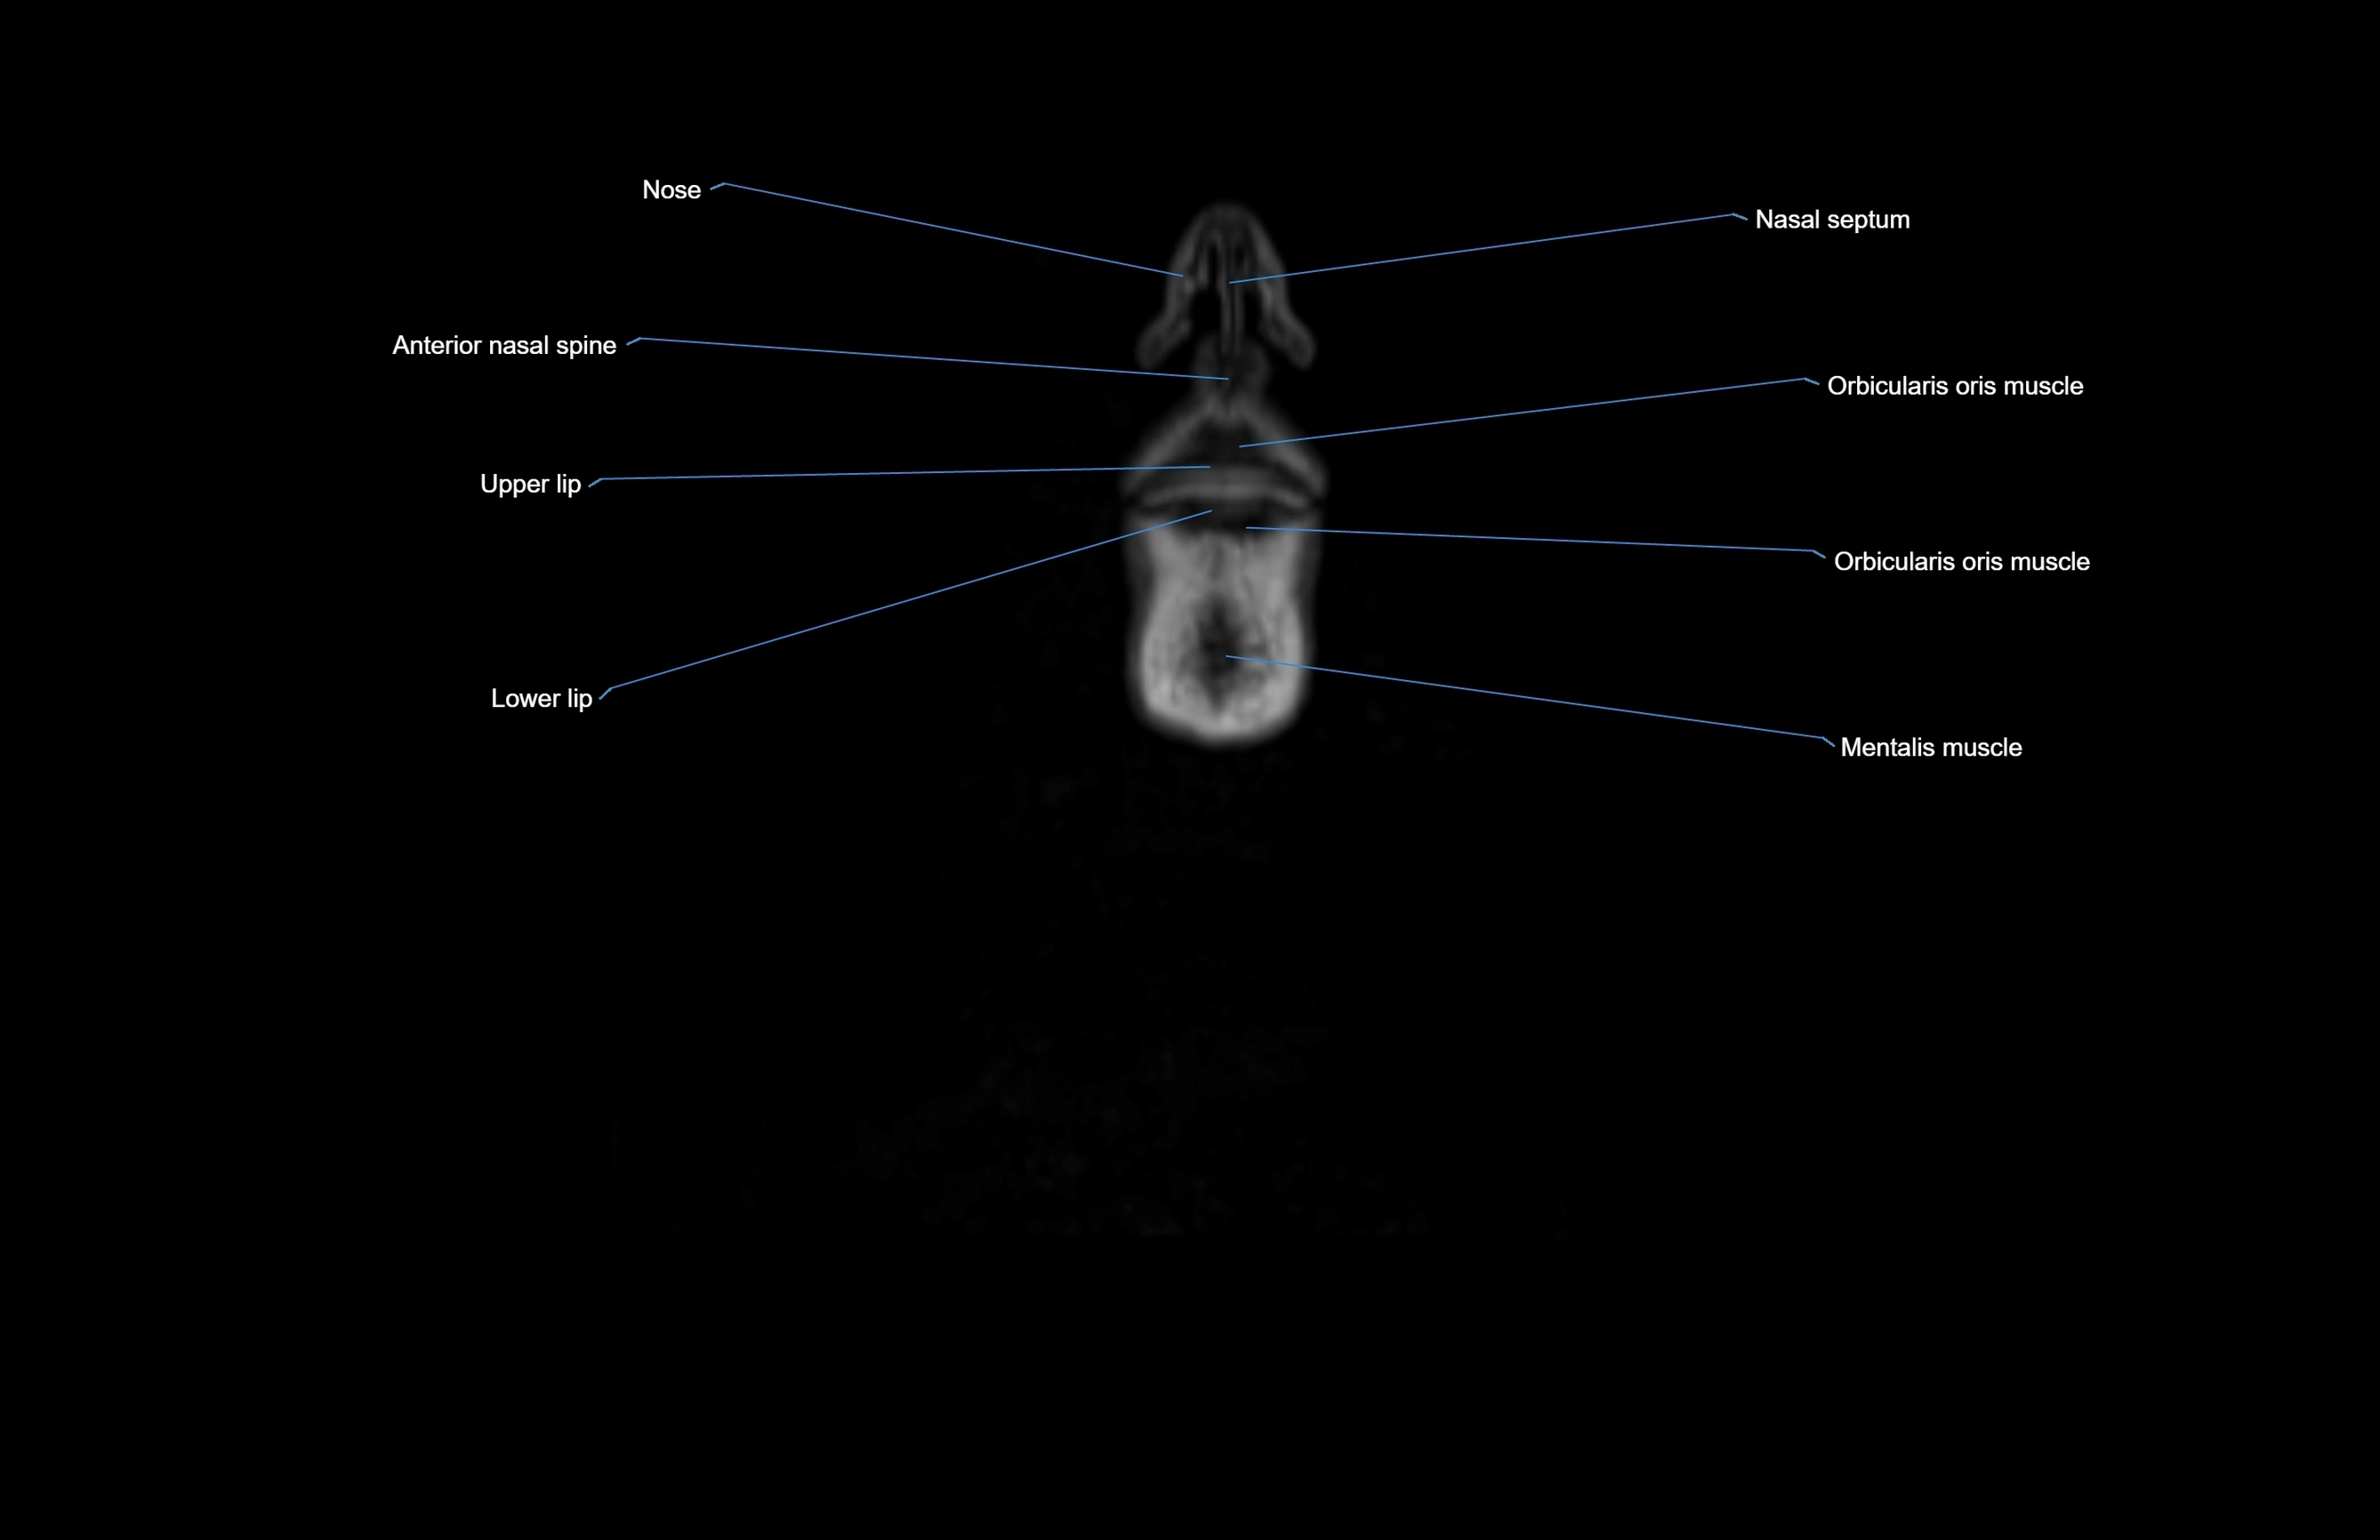

MRI images